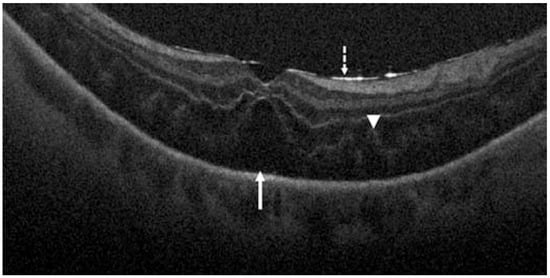

- Takahashi, H.; Tanaka, N.; Shinohara, K.; Yokoi, T.; Yoshida, T.; Uramoto, K.; Ohno-Matsui, K. Ultra-Widefield Optical Coherence Tomographic Imaging of Posterior Vitreous in Eyes With High Myopia. Am. J. Ophthalmol. 2019, 206, 102–112. [Google Scholar] [CrossRef]

- Schranz, M.; Roberts, P.K.; Motschi, A.R.; Hollaus, M.; Mylonas, G.; Sacu, S.; Pircher, M.; Hitzenberger, C.K.; Schmidt-Erfurth, U. Tracking of fibrosis growth in neovascular age related macular degeneration. Investig. Ophthalmol. Vis. Sci. 2022, 63, 1025–F0272. [Google Scholar]